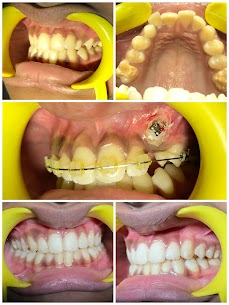

Fast Braces with Surgical Intervention

- INFO:

12-month treatment for 14-year-old with unerupted canine, including surgical exposure